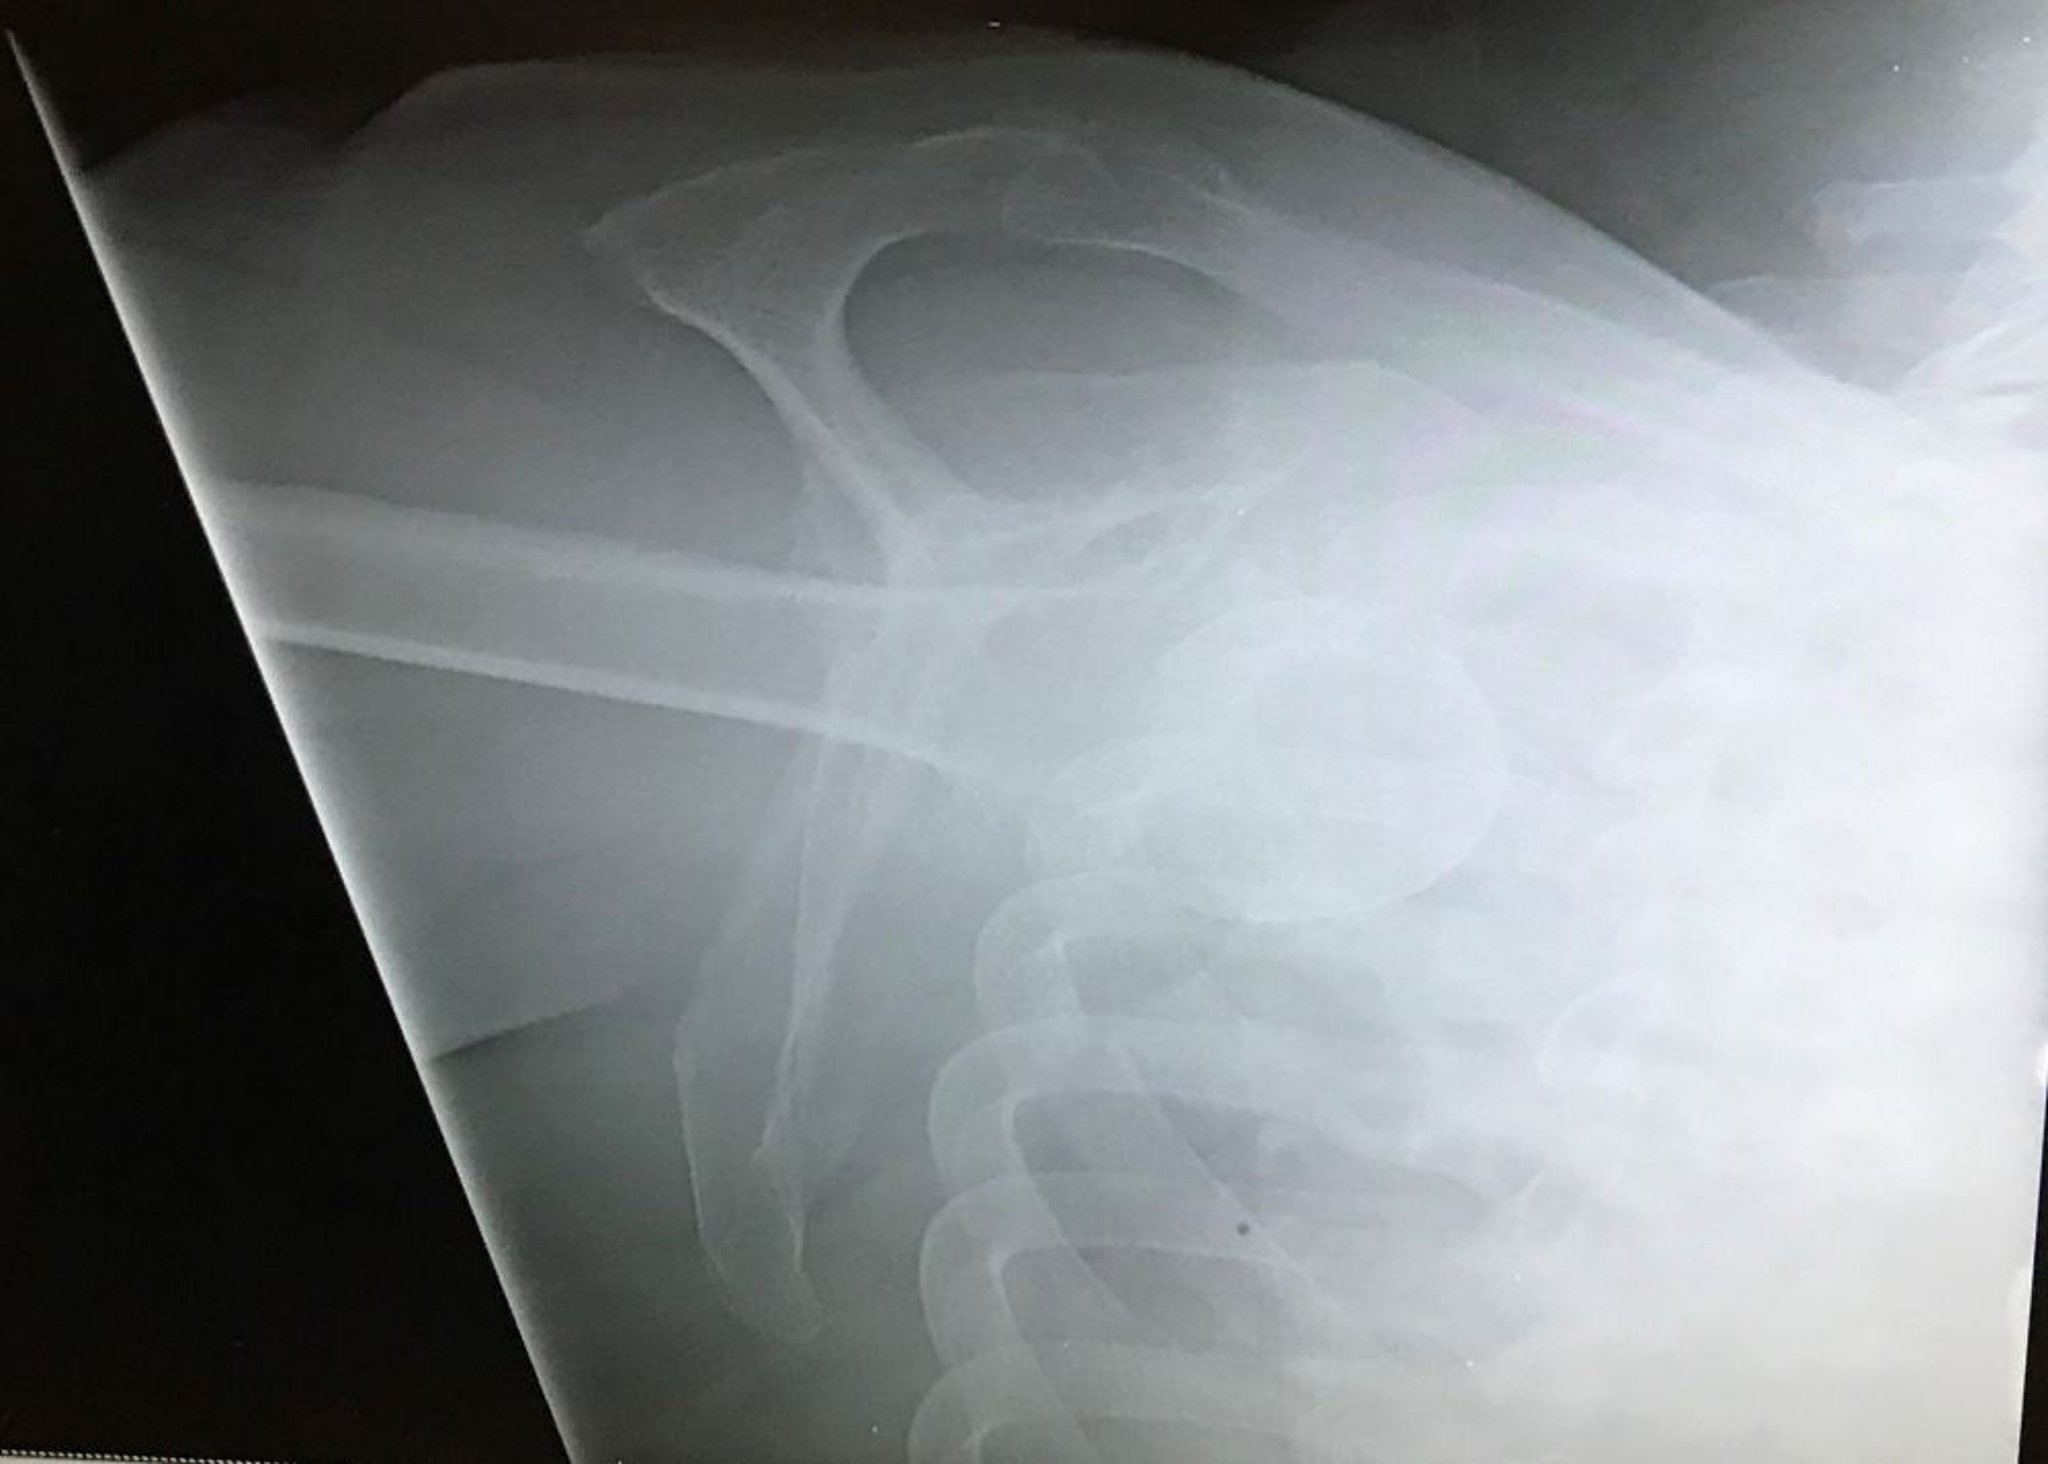

Inferiore Schulterluxation

Diese Y-Ansicht der Schulter zeigt den Humeruskopf unterhalb der Fossa glenoidalis mit dem mit der Extremität ausgerichteten Kopf, was auf eine inferiore glenohumerale Luxation (luxatio erecta) hinweist.

Image courtesy of Danielle Campagne, MD.